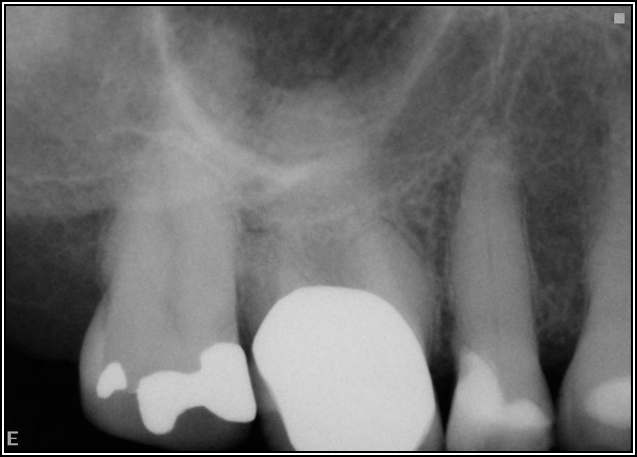

If a tooth stands alone, greater forces will be placed on it because it has no adjacent teeth to provide support. This situation will affect the decision-making process for placing a post. Figure 3 shows a tooth that was on an island and would be having three implants placed in front of it. The tooth would take a much greater beating than another tooth that had support proximally. Even though it had a good root canal, the clinician would need to account for whether the tooth would last until the implants integrated. Figure 4 shows a case that would quickly proceed to implants. The patient had a less-than-ideal bridge for over a decade, with decent endodontics and functionality. There was also an overhang on the premolar. The post was not ideal in this case because there was one distal canal and not all the gutta-percha was removed from it. An intimate fit should be the goal with the post and the walls. Whether using a threaded or non-threaded post, there should not be excess gutta-percha because it is not as solid as the tooth and will lead to greater movement. That movement on the tooth and bridge will create too much force and result in demise.

Fig 3. Tooth on an island.

Figure 3

Fig 4. Case that quickly would proceed to implants.

Figure 4